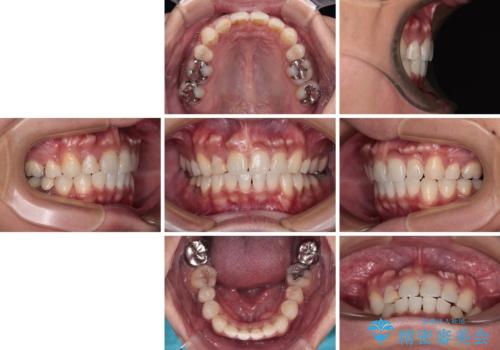

【モニター】八重歯と正中のずれた歯列 片顎抜歯のワイヤー矯正

- 上顎の八重歯と正中のズレを気にして来院された患者様です。

八重歯による叢生は著しく、それにより上顎の正中が大きく右にずれている状態でした。

口元の突出感は感じていなかったことと、奥歯の咬み合わせを考慮し、上顎のみ左右の第一小臼歯を抜歯してワイヤー装置にて矯正治療を行うこととしました。

補助装置を併用することで効率的に八重歯や正中位置の改善を達成することができました。